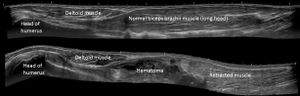

Panoramic ultrasonography